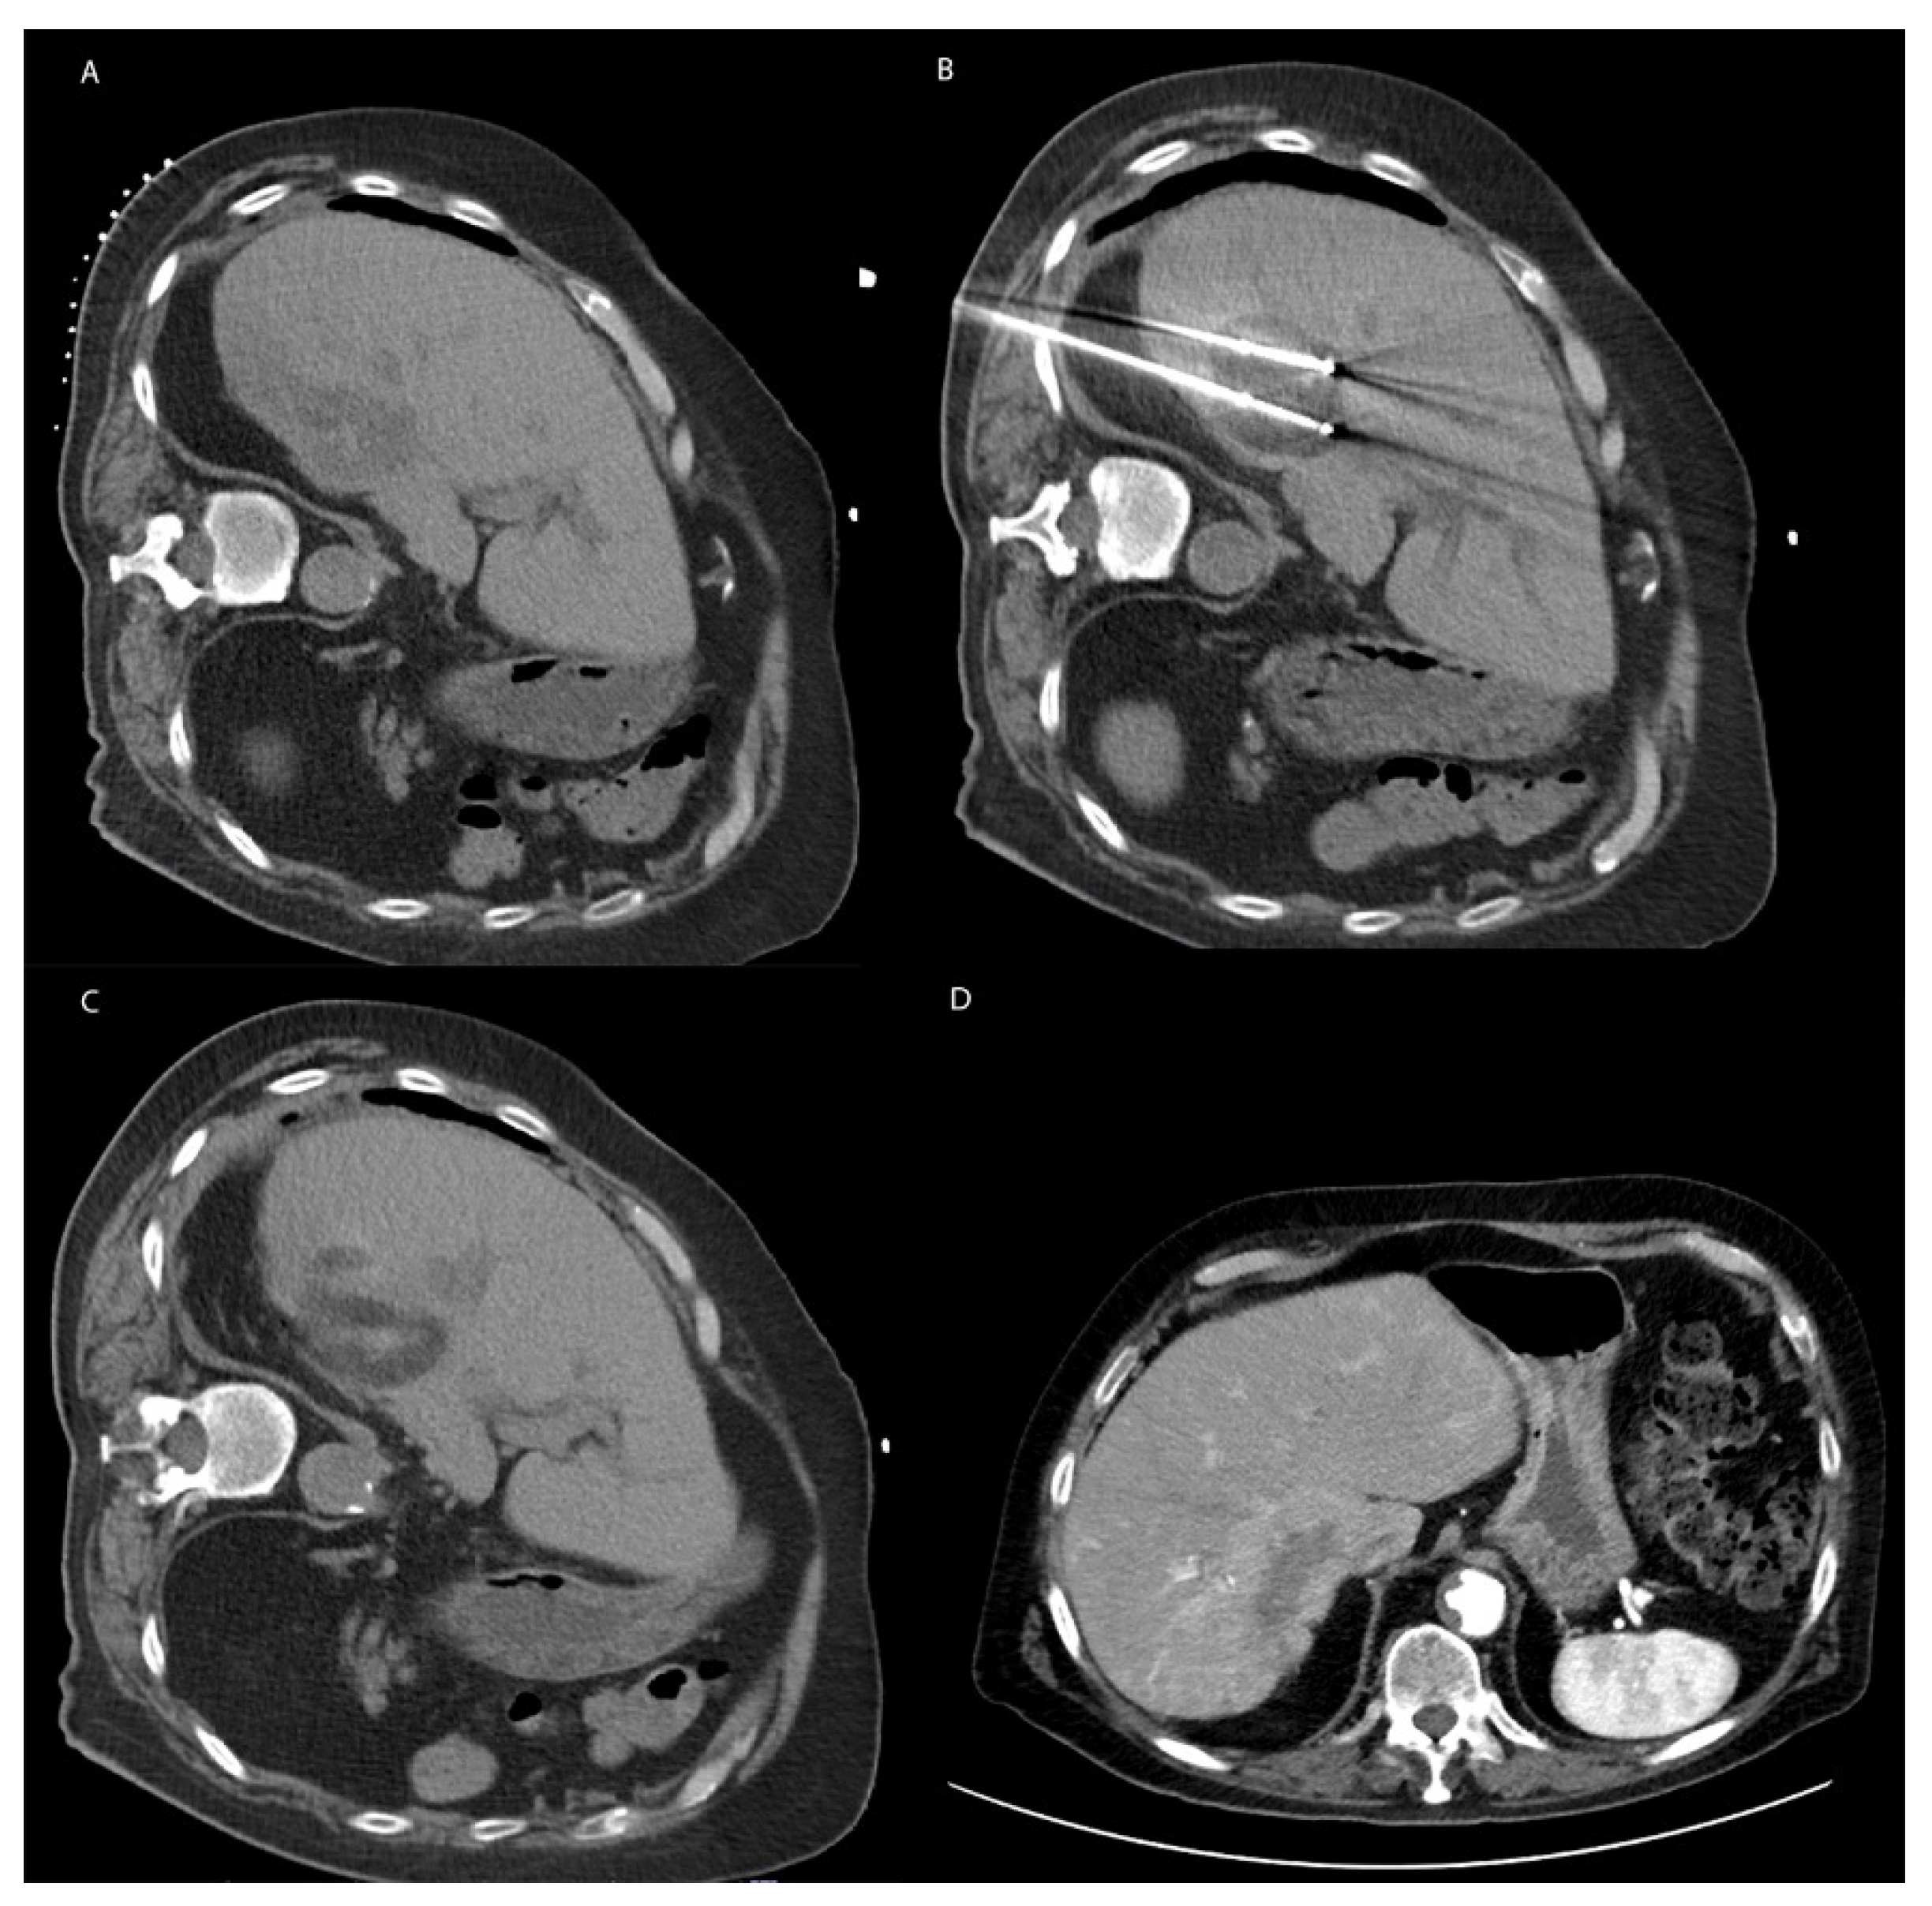

8. Irreversible Electroporation

8.1. Technique

8.2. Irreversible Electroporation in Non-HCC Primary Liver Malignancy and Metastatic Disease to the Liver